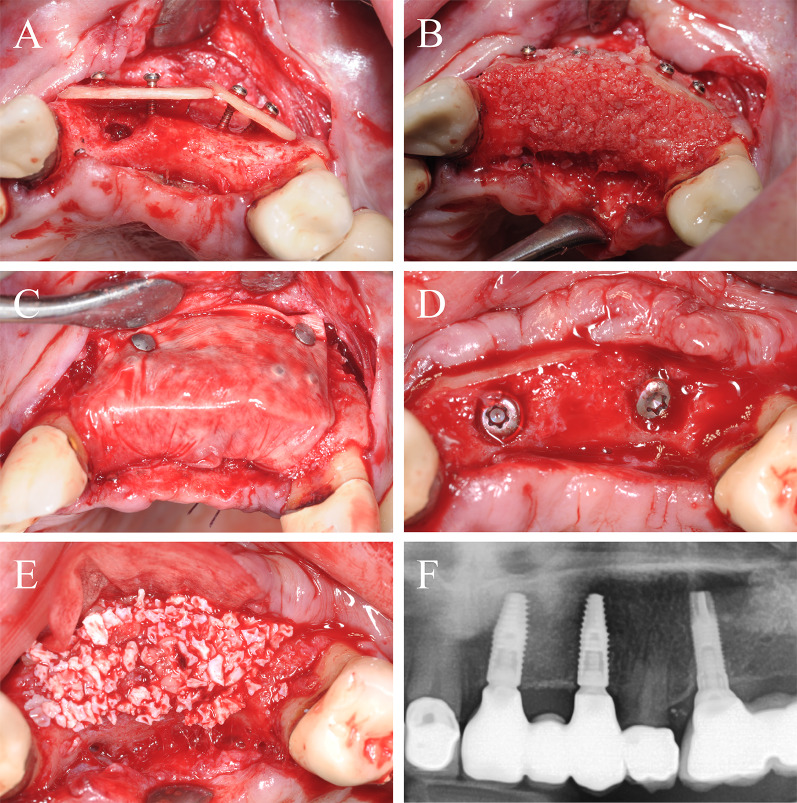

A 64-year-old patient with multiple missing teeth in the anterior maxilla was referred for implant-borne prosthetic rehabilitation. After clinical and radiological examination, the regions 21–23 showed a severe horizontal bone atrophy preventing implant placement in the intended prosthetic position. A mucoperiosteal flap was raised after crestal incision. The incision line was extended marginally from 13 to 25 with vertical releasing incision distally for tension-free wound closure and to avoid further scars in the esthetic area. First, a CP was split into two fragments. The fragments were attached to the jaw by 1 mm adjusting screws in a curvy line to imitate the new outer contour of the maxilla in regions 21–23 (Fig. 4A). The space between the CP and the native bone was then filled with allogeneic granules (Fig. 4B). The defect site was covered with a barrier membrane and fixed by titanium pins (Fig. 4C). The wound was closed by a combination of horizontal-mattress and single-button sutures. After 4 months, re-entry was performed and the augmented site was uncovered (Fig. 4D). CP were well integrated into the new formed bone tissue and merely visible at re-entry. After recontouring sharp sites of the CP and removing the screws and pins the grafting volume was still well maintained, allowing the insertion of two dental implants (BLT, 4.1 × 12 mm, Straumann) in the correct position according to the treatment plan. Afterwards, bovine BS was used for relining of the grafted area to prevent resorption of the new formed crest and increase the volume stability in the long-term (Fig. 4E). The grafted site was again covered with a pericardium collagen membrane. Following another 4 months, the implants were uncovered, and healing abutments were installed along with a modified apically repositioned flap in combination with roll-flaps and gingival tuber transplantation in region 22 to increase the thickness of attached keratinized gingiva. After another 2 months of healing, the final dental bridge was installed by the referring general dentist (Fig. 4F). Within the follow-up of 25 months, the case remained stable without complications.

Fig. 4.

Alveolar ridge augmentation of the anterior maxilla. A Initial intraoperative situation with an extended alveolar defect of the anterior alveolar jaw. Two allogeneic cortical bone plates were fixed by fixation screws. B Intraoperative situation after filling the defect with allogeneic spongious granules. C Covering the augmented area with a porcine collagen membrane. D Implant placement 4 months later. E Overlining with xenogeneic bone graft to preserve the volume of the augmented area. F X-ray demonstrating inserted implants